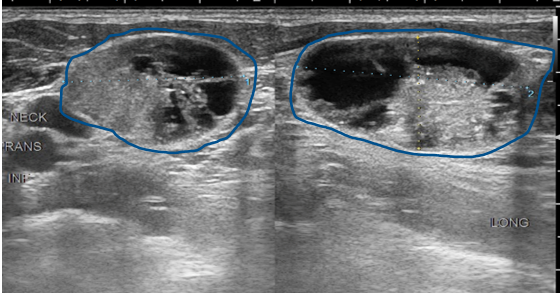

Thyroid ultrasound scans are safe and effective ways to produce images of the thyroid gland. Transverse grey scale sonogram shows a solid ill-defined hypoechoic nodule arrows containing punctate calcification arrowheads in the right lobe of thyroid gland. Thyroid nodules were found in 97 of patients with thyroid cancer and in 56 of without.